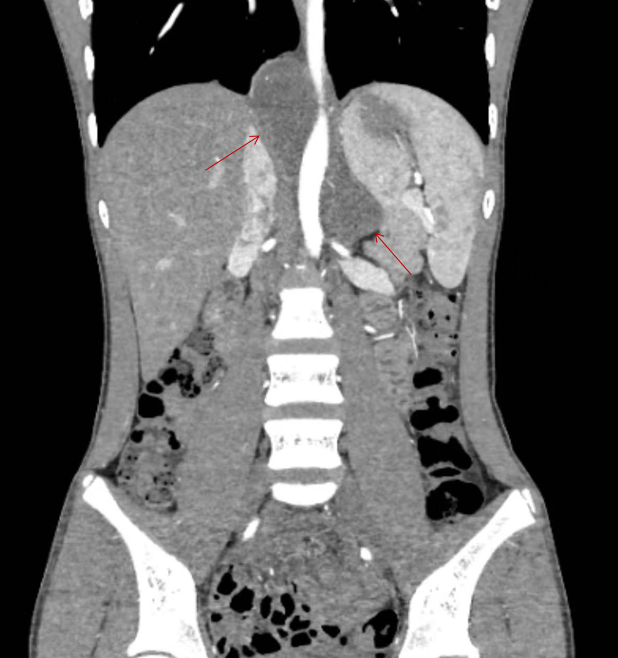

术前增强CT提示腹膜后及后纵隔两处病变(箭头处)

检查发现,小严左侧肾上腺区和右后下纵隔胸腹交界处各有一处约5.5cm大小的病变,考虑为左侧肾上腺神经母细胞瘤并局部转移。传统手术需要分别经胸、经腹做两个大切口,创伤大、恢复慢。即使在腔镜技术比较成熟的现在,一般也需要分别经胸腔镜和腹腔镜各做3个或3个以上的小切口才能完成手术。经过仔细阅片,武玉睿决定尝试经腹小切口单孔腹腔镜手术切除所有病变,这一术式此前尚无同行尝试。2月12日,主管医生郑启鹏详细向家长做了病情解释和术前谈话,取得了家长的充分信任。